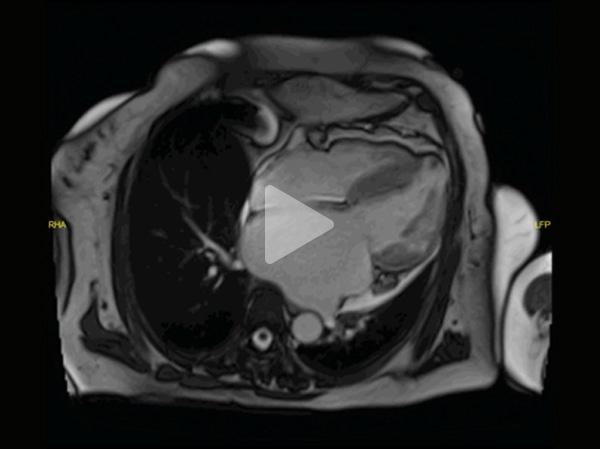

Vidéos 3 et 4 : Petite cavité VG, oreillettes dilatées - Anévrysme apical - Thrombus apex et auricule

Vidéo 3

Vidéo 4